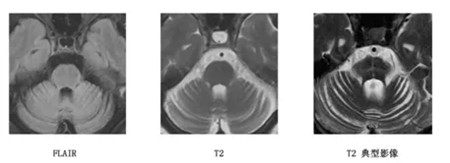

多系统萎缩(Multiple System Atrophy,简称MSA)是一种罕见的散发性、原因不明的进行性神经系统变性疾病,主要影响身体的多个系统,包括自主神经系统、运动系统以及泌尿生殖系统等。